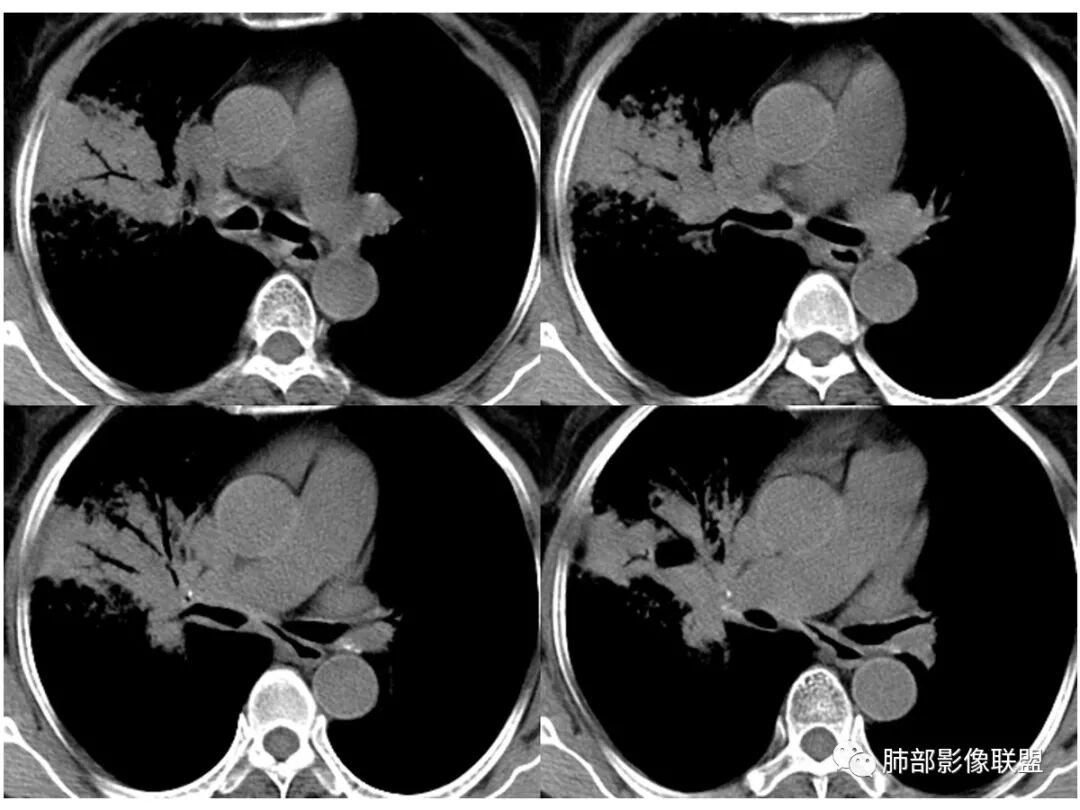

老年女性,右肺上叶大片实变及磨玻璃密度影,磨玻璃边缘清晰,内可见小叶间隔增厚,内可见空洞,似可见分隔,叶间裂局部膨隆,纵膈窗,没有增强,枯树枝不明显,肺炎型肺癌可能,鉴别大叶性肺炎,结核?

胸CT:右肺上叶实变内可见支气管充气征,近端支气管狭窄,远端扩张,周围可见毛玻璃影,右肺中叶支气管闭塞,并可见气道壁钙化,右肺中叶体积缩小,实变内可见空洞,并可见气液平面,空洞周围可见毛玻璃样影,右肺下叶支气管开口狭窄,右肺门淋巴结肿大。纵隔窗可见病灶与壁层胸膜间隙增宽,考虑良性病变-----感染性病变------TB?

右中叶支气管完全阻塞伴厚壁空洞,右上叶支气管不全阻塞伴大片GGN,右下部分GGN考虑腺鳞癌,结核待排。

主病灶应该是粘腺腺癌,右中叶不张?,内空洞,壁光滑,考虑感染

纵隔窗,没有看到太多细支气管里粘液的密度。

如果有增强,对诊断有帮助吗?粘液腺癌有粘液不强化,结核多发灶样坏死也不强化,血管观察有时也不好鉴别,最怕结核是增殖与坏死并存,难啊

良孑:

如果有强化,对诊断鉴别有帮助,TB坏死彻底不强化,粘液腺癌的粘液因含肿瘤细胞可不均匀强化,另外CT造影的血管征可与TB鉴别